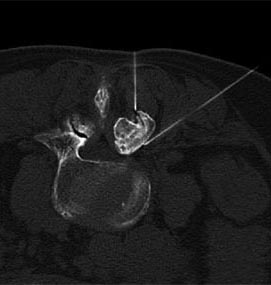

Zur Eingriffsplanung und Steuerung der Mikrotherapie werden die CT und die digitale Röntgendurchleuchtung verwendet. Durch diese Art der Planung und Kontrolle ist ein millimetergenaues Vorgehen möglich. Auf diese Weise wird die Verletzung wichtiger anatomischer Strukturen und Organe vermieden. Je nach Art des Eingriffs kann eine Kontrolle der Instrumente auch über ein Endoskop mit Glasfaserkabeln und Lichtleitern erfolgen.

Die korrekte Lage der Instrumente wird kontrolliert und ggf. korrigiert. Je nach Befund (bei der Halswirbelsäule relativ oft) muss die Instrumenten- oder Nadellage mittels der Gabe einer geringen Kontrastmittelmenge kontrolliert werden. An der Lendenwirbelsäule wird der Eingriff in Bauchlage durchgeführt, an der Halswirbelsäule in Rückenlage. Die Infiltration mittels Nadeln wird auch als diagnostisches Verfahren, als sogenannte Testinfiltration genutzt.

Abbildungen: rechts unten: Selektive Infiltration des Kreuzdarmbeingelenks (ISG), links oben: Mikrotherapie am Facettengelenk mit Kontrolle der Nadellage am Gelenkspalt, zweite Nadel im Wurzelkanal